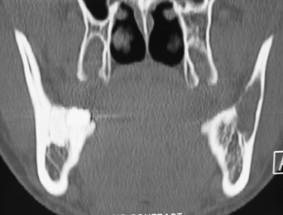

The traumatic bone cyst (TBC) is an uncommon nonepithelial lined cavity of the jaws. The lesion is mainly diagnosed in young patients most frequently during the second decade of life. The majority of TBCs are located in the mandibular body between the canine and the third molar. Clinically, the lesion is asymptomatic in the majority of cases and is often accidentally discovered on routine radiological examination usually as an unilocular radiolucent area with a "scalloping effect". The definite diagnosis of traumatic cyst is invariably achieved at surgery. Since material for histologic examination may be scant or non-existent, it is very often difficult for a definite histologic diagnosis to be achieved. We present a well documented radiographically and histopathologically atypical case of TBC involving the ramus of the mandible, which is also of possible iatrogenic origin. The literature is briefly reviewed.

创伤性骨囊肿(TBC)是一种罕见的、无上皮衬里的颌骨腔隙。该病变主要在年轻患者中被诊断出来,最常见于生命的第二个十年。大多数TBC位于下颌骨体部,在尖牙和第三磨牙之间。临床上,在大多数病例中该病变无症状,通常在常规放射学检查时偶然发现,表现为单房性透射区,具有“扇贝样效应”。创伤性囊肿的明确诊断总是在手术时才能实现。由于用于组织学检查的材料可能很少或不存在,因此往往很难做出明确的组织学诊断。我们报告一例有充分影像学和组织病理学记录的非典型TBC病例,累及下颌支,其可能也有医源性起源。并对相关文献进行简要综述。